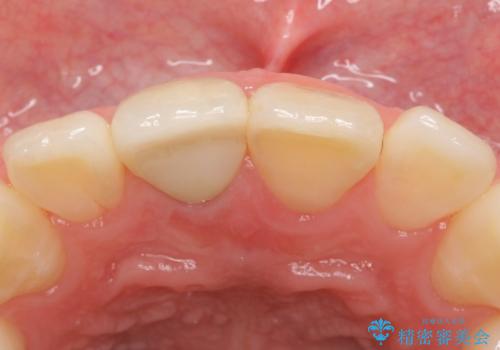

- 右上1番目の前歯の変色が気になるといらっしゃった方の症例です。

再根管治療後、オールセラミッククラウンによる補綴を行いました。